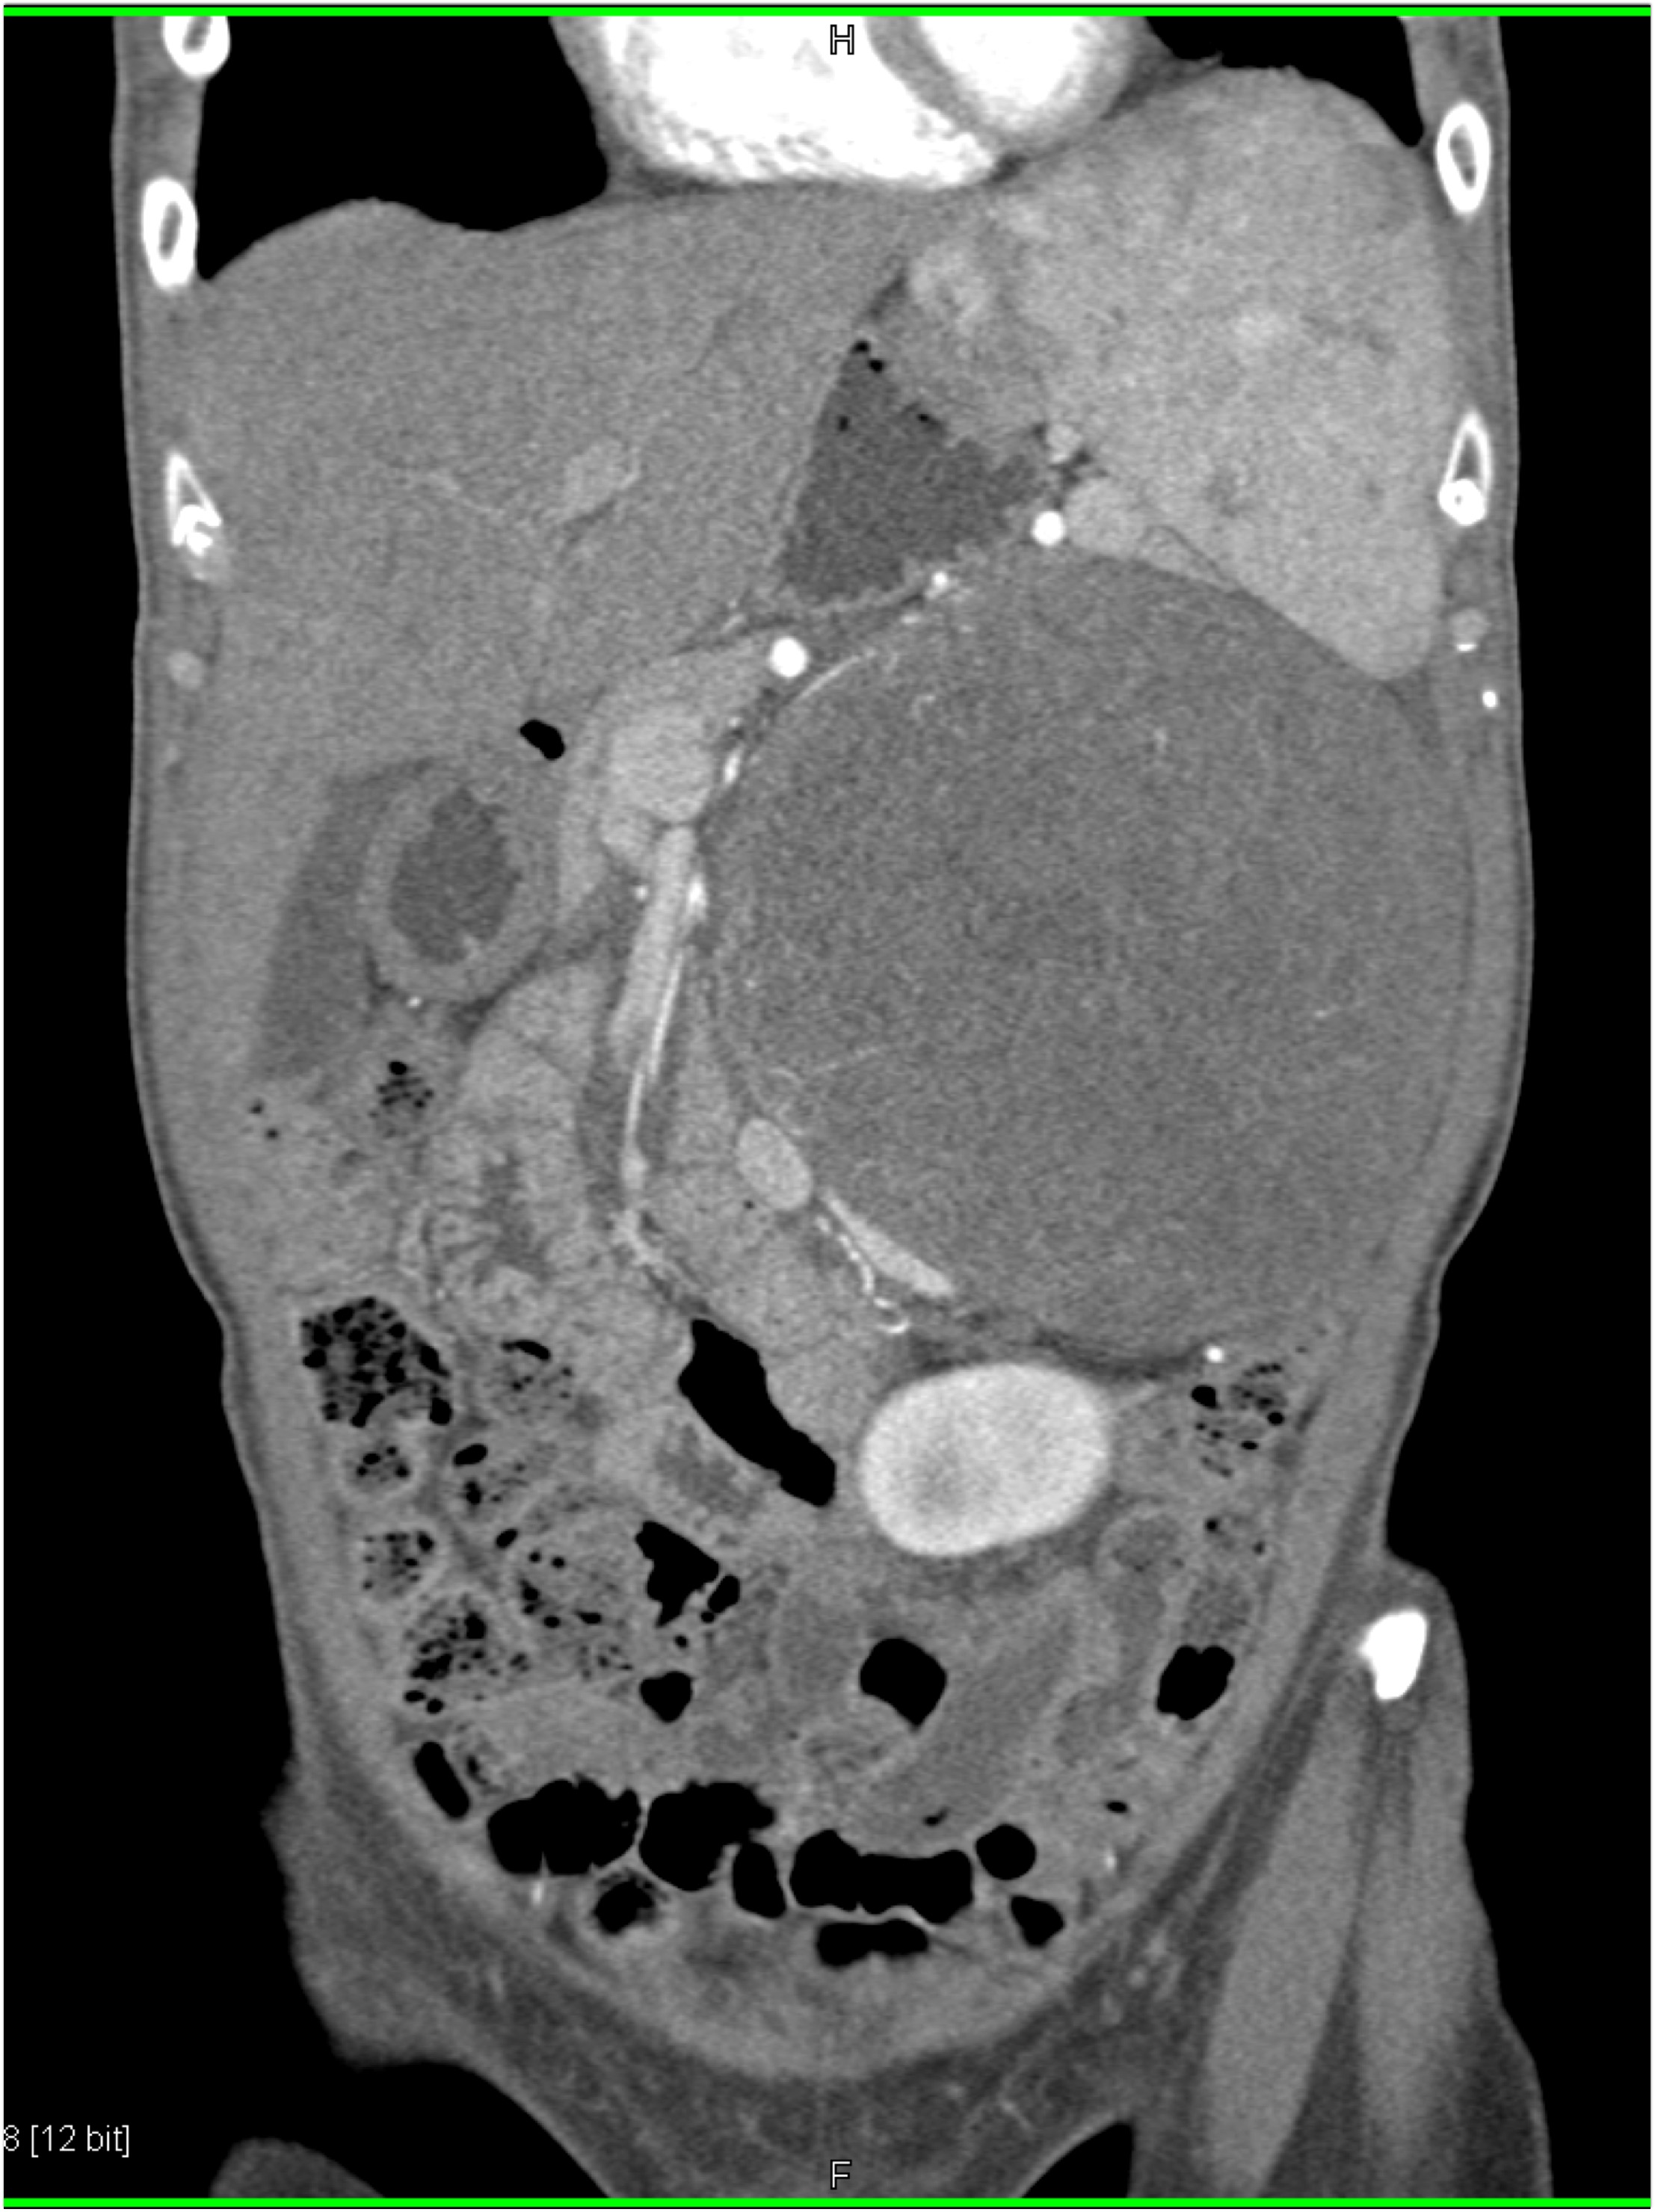

1) The most likely diagnosis in this patient with LUQ pain is?

adrenal myelolipoma

adrenal ganglioneuroma

adrenal adenoma

pheochromocytoma